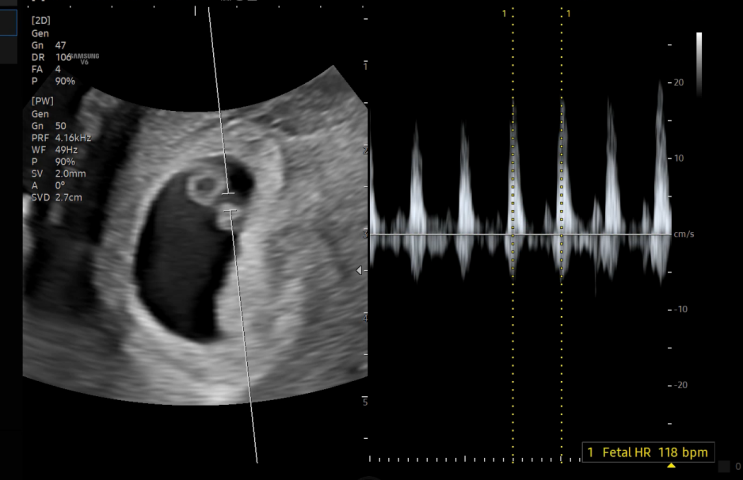

[임신 6주] 입덧시작, 초음파 아기심장소리 듣는 시기 언제?

임신 6주차 4주차 아기집을 보고 12주 안정기가 되기까지는 2주간격으로 방문 그 사이 복직을하고 회사에 ...